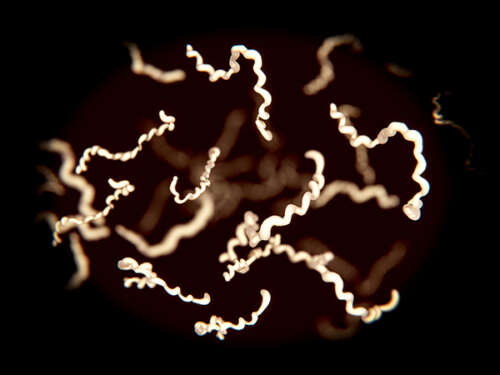

Is Lyme disease a government-made bioweapon?

(Natural News) There is a new epidemic of Lyme disease, or so we are told, that is once again drawing attention to the claim of award-winning author Kris Newby, whose book “Bitten: The Secret History of Lyme Disease and Biological Weapons” suggests that Lyme disease is a government-made bioweapon. Dr. Joseph Mercola addressed this in…